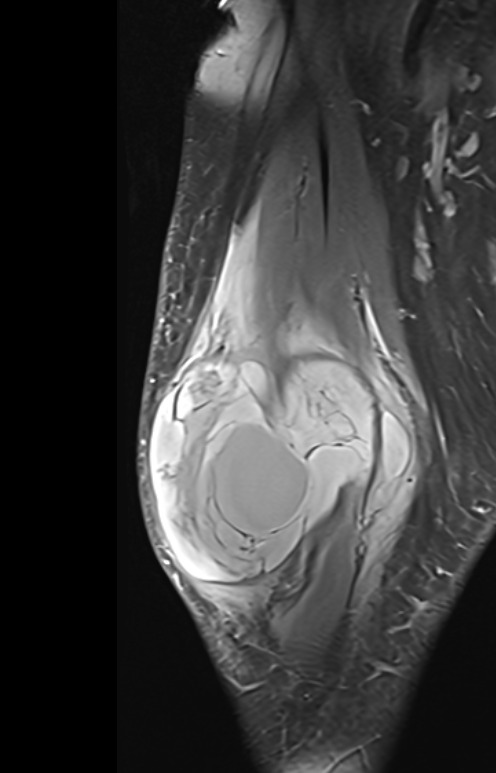

Muscle Cancer